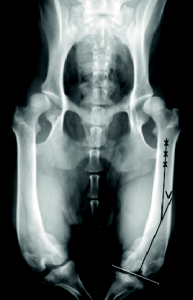

Pri prizadetih mladičih kosti med rastjo pod vplivom neprimernih sil vleka nepravilno rastejo. Te sile nastanejo primarno zaradi premajhnega kota med glavico in vratom stegnenice ter vzdolžno osjo stegnenice, tako imenovana coxa vara. Posledica kolčne napake je popačeno delovanje ekstenzornega mehanizma, ki ga sestavlja velika štiriglava stegenska mišica (musculus quadriceps), ki se končuje s pogačično kito, v katero je vpeta pogačica. Kita se prirašča na golenično grčo oziroma tuberkel (Slika 1). Mehanizem bi moral potekati v ravni liniji od zgornjega dela stegnenice do sredine golenice (Slika 1).

Četrta stopnja: pogačice se ne dá reponirati nazaj v žleb. Spremljajo jo hujša ukrivljanja golenice in stegnenice, zasuk golenice za več kot 60 stopinj, odsoten ali celo konveksen interkondilarni žleb. Zelo izrazito je šepanje ali hoja v polčepečem položaju (Slika 2).

Veterinar bo opravil ortopedski pregled, pri katerem lahko odkrije izpah pogačice. Nato opravi rentgensko slikanje, ki v takih primerih zadošča (Slike 3 do 8). V težjih primerih se poslužujemo tudi računalniške tomografije (CT-ja).

V redkih primerih, ko je izpah ocenjen s prvo stopnjo ali ko je psiček brez očitnejših sprememb na skeletu zadnje noge, se lahko odločimo za konzervativno zdravljenje: krepitev mišičja, fizioterapija. V nekaterih primerih to pomaga, v vseh drugih pa svetujemo , na primer, kombinacijo različnih operativnih tehnik, s katerimi rekonstruiramo normalno anatomsko lego ekstenzornega mehanizma zadnje noge oziroma se poskušamo temu kar najbolje približati. Večino izpahov saniramo s tako imenovano trohleoplastijo (poglabljanje interkondilarnega žleba, v kateri bi morala ležati pogačica) in transpozicijo (prestavitvijo) golenične grče (Slike 7a, b in c). Okolna mehka tkiva prilagodimo s tehnikami ojačevanja mišičnih ovojnic okrog kolenskega sklepa in s sproščanjem določenih mišičnih skupin. Zgolj z ojačevanjem mehkih tkiv brez korekcije kosti in prirastišč pomembnih kit ne dosežemo zadovoljivega rezultata, saj silam vleka kosti ne moremo botrovati samo s silami mišičja.

V težjih primerih (četrta stopnja izpaha) opisane tehnike nadgrajujemo z dodatnimi potrebnimi posegi, in sicer z osteotomijo stegnenice ali/in golenice prizadete noge.